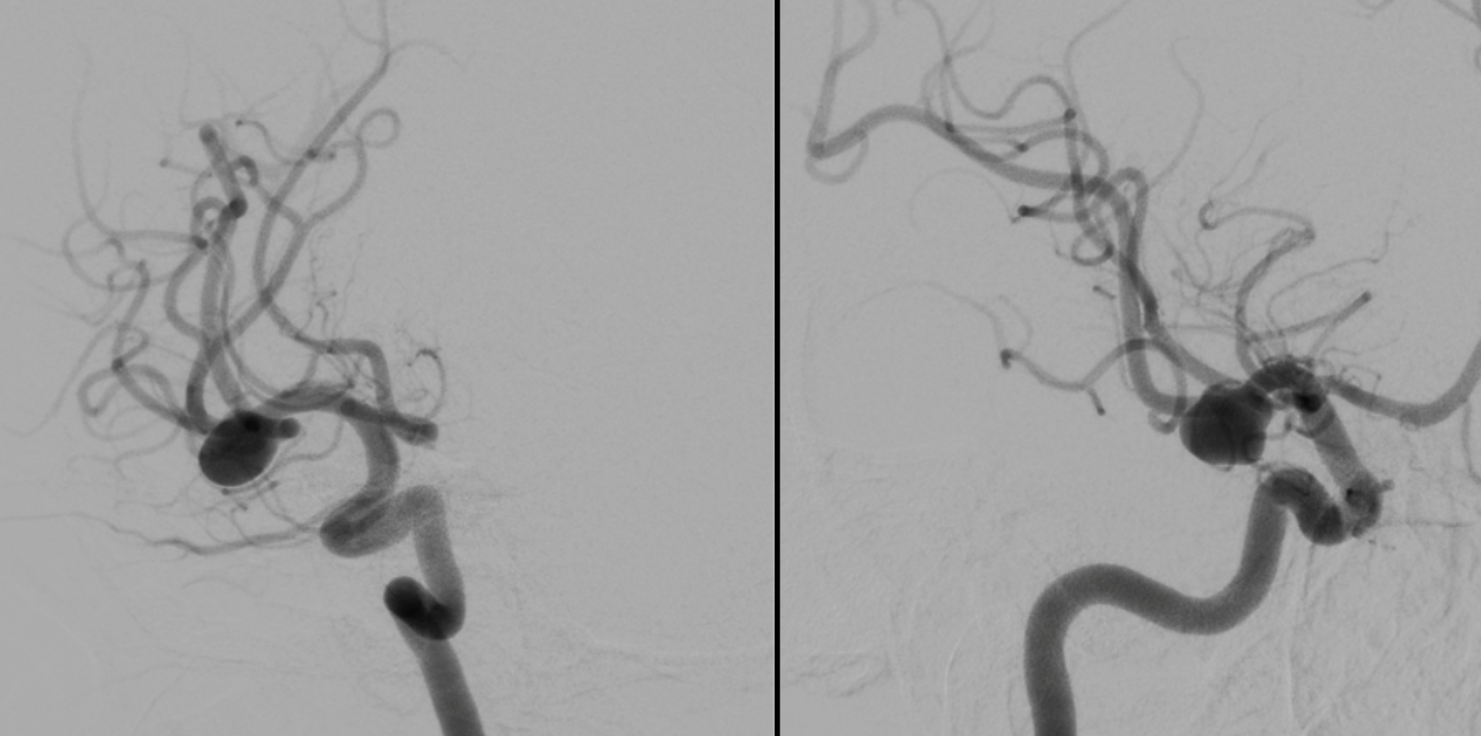

A symptomatic unruptured MCA bifurcation aneurysm in a young woman

This video was made with Horos from the original 3D dataset (3D 5 seconds 15 cm FOV acquisition, manually injecting pure contrast – 250 mg/ml – with a 20 ml syringe).